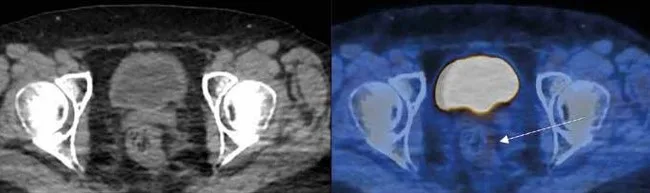

Évaluation de la réponse au traitement du cancer rectal (Figure 1)

Dans le cancer rectal, la TEP au FDG présente de très bonnes performances, notamment de spécificité pour l’évaluation de l’atteinte ganglionnaire des aires iliaques internes, externes et obturatrices, atteintes fréquentes dans les lésions du bas rectum ou les lésions T3-T4 [14].

Les méta-analyses de Maffione et al. et Rymer et al. [15,16] ont retrouvé de bonnes performances de la TEP FDG pour prédire la réponse histologique complète après radio-chimiothérapie néoadjuvante, permettant d’identifier les bons répondeurs et conduisant certaines équipes à proposer à des patients en réponse métabolique complète, une stratégie attentiste afin d’éviter une chirurgie radicale [17]. Une étude souligne l’intérêt de la réalisation précoce de la TEP FDG pour l’évaluation de la réponse [18].

La TEP au FDG présente de bonnes valeurs de sensibilité et de spécificité pour évaluer l’efficacité de la radio-chimiothérapie dans le cancer du rectum et identifier les patients qui présentent une réponse complète.

La TEP au FDG peut être proposée à la fin du traitement de radio-chimiothérapie du cancer du rectum pour évaluer la réponse au traitement.

Figure 1 : TEP préthérapeutique chez une patiente présentant un cancer du rectum :

Figure 1a : Lésion hypermétabolique rectale très intense (Standardized Uptake Value : SUV max=9.5), flèche rouge.

Figure 1b : Réponse métabolique complète sur la TEP de fin de traitement de radiochimiothérapie, flèche blanche.